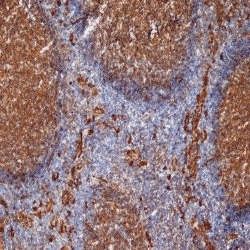

WB (Western Blot), FCM/FACS (Flow Cytometry), IHC (Immunohistochemistry)

Mouse anti Human CD9 antibody, clone MM2/57 recognizes human Leukocyte antigen MIC3 also known as MRP-1 or CD9. CD9 is a 228 amino acid multi pass membrane glycoprotein belonging to the tetraspanin family with a molecular weight of ~24kDa expressed by platelets, monocytes, some lymphocytes and endothelial cells. Mouse anti Human CD9 antibody, clone MM2/57 recognizes a conserved epitope on CD9 present on a wide range of mammalian species.